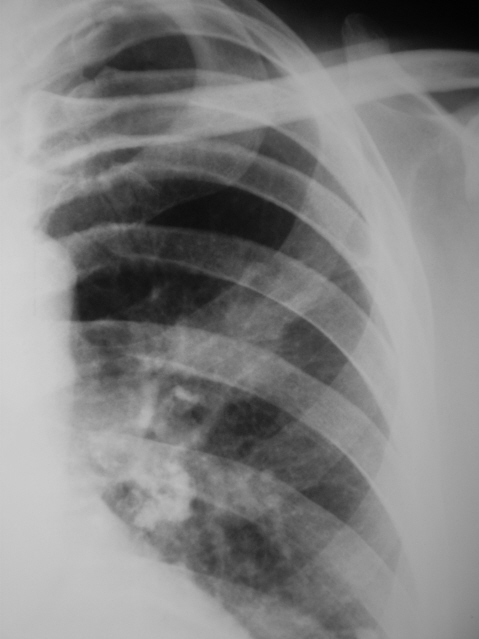

Пациент в течение ряда лет не проходил профилактической флюорографии. После расшифровки флюорограмм "взят на контроль". Произведена рентгенография и линейная томография в прямой проекции.

Несмотря на наличие "архива" в виде обызвествленных лимфатических узлов склоняюсь в пользу рака.

Публикации: 18098

Я бы оставил два диагноза, и порекомендовал бы бронхоскопию. В советские времена слушал сообщение о ТВС бронхов. Рентгенологически - типичные раковые ателектазы. Даже патоморфология неоднозначна. Эффект - при противотуберкуллезной терапии екс ювантибус.

Валентин Львович! Упустил случай! Как меня учили, "туберкулез" с "раком" вместе не живут. Но в Вашем случае очень похоже на опухолевый процесс на фоне туберкулезных изменений.

Согласен, что это два процесса, и последнее время такое встречается довольно часто.